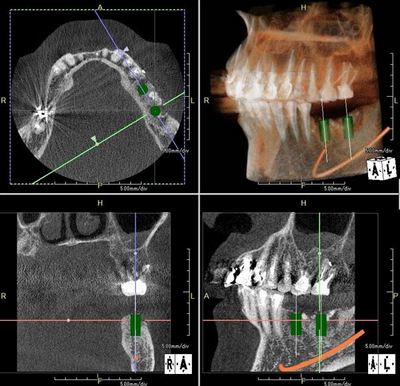

左下大臼歯2本の部分にインプラントを2本埋入します。

歯科用CTファインキューブによるインプラントシミュレーションです。